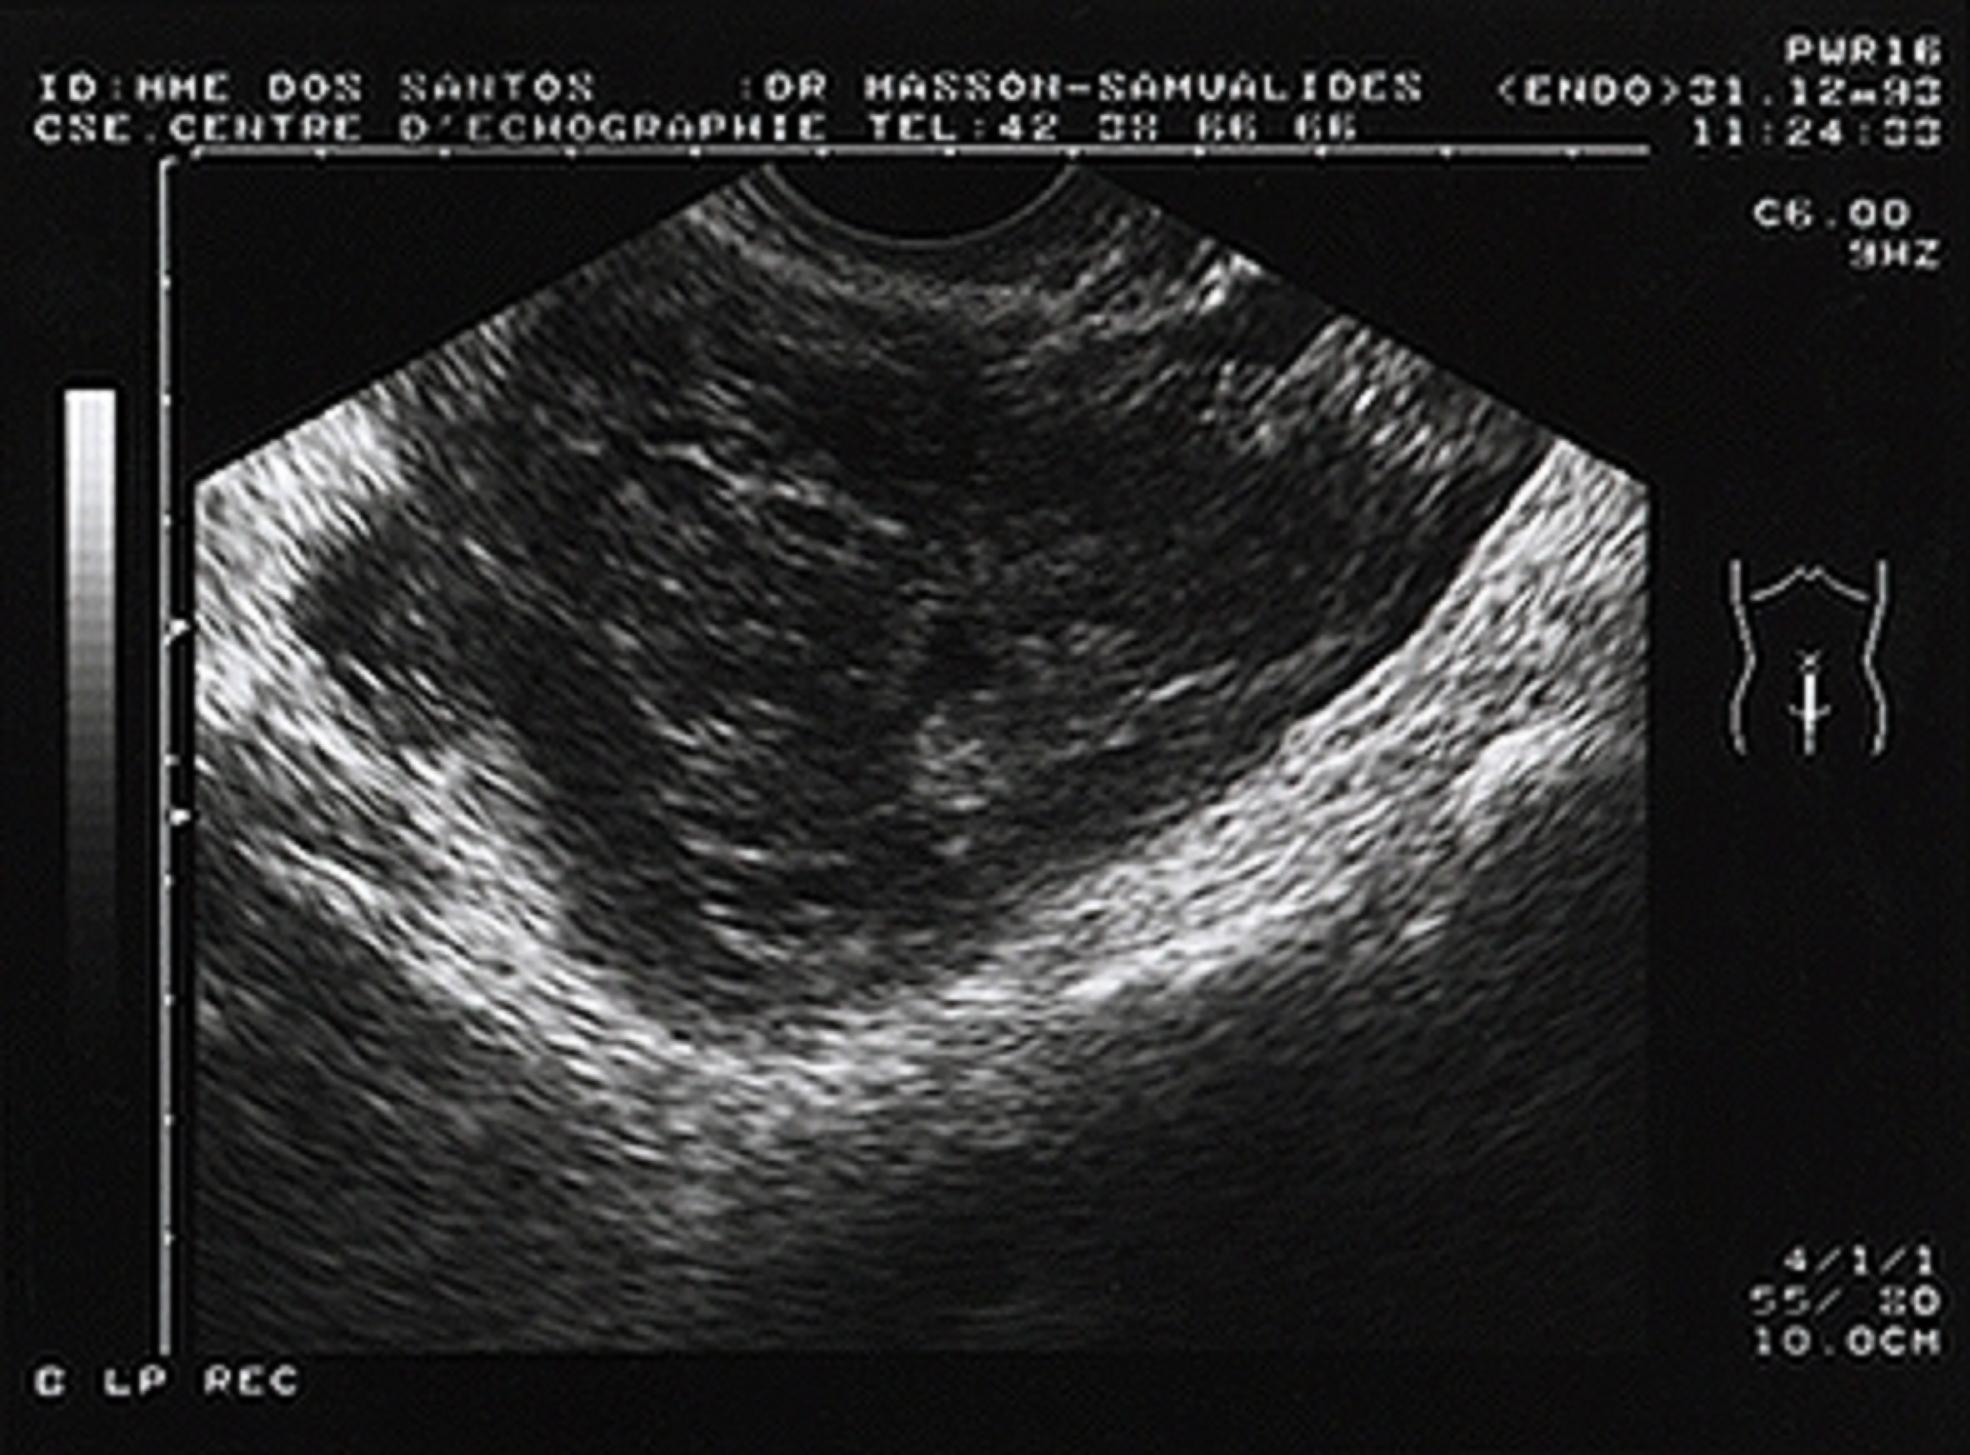

Échographie : Pratiquée au mieux par voie endovaginale, elle recherchera une abcédationDéfinitionÉvolution locale d'une lésion infectieuse aboutissant à la constitution d'un abcès. : pyosalpinxDéfinitionPrésence de pus dans une trompe utérine ou dans les deux. Un pyosalpinx est la conséquence d'une salpingite (inflammation d'une trompe ou des deux, d'origine infectieuse) non diagnostiquée ou traitée trop tardivement. Il se manifeste par des douleurs pelviennes importantes, rendant l'examen gynécologique difficile. Un pyosalpinx entraîne un risque de stérilité par obturation des trompes. Le diagnostic est confirmé soit par échographie pelvienne, soit par cœlioscopie. Le traitement consiste à drainer le pus et à réparer la ou les trompes éventuellement endommagées, voire à les retirer chirurgicalement (salpingectomie). Selon les cas, l'intervention peut faire appel aux techniques de la cœliochirurgie (introduction des instruments chirurgicaux par de petites incisions abdominales) ou nécessiter une laparotomie (ouverture chirurgicale de l'abdomen)., abcès ovarien, abcès du Douglas. En l'absence de collection, l'échographie sera le plus souvent normale.

Aspect échographique d'un pyosalpinx